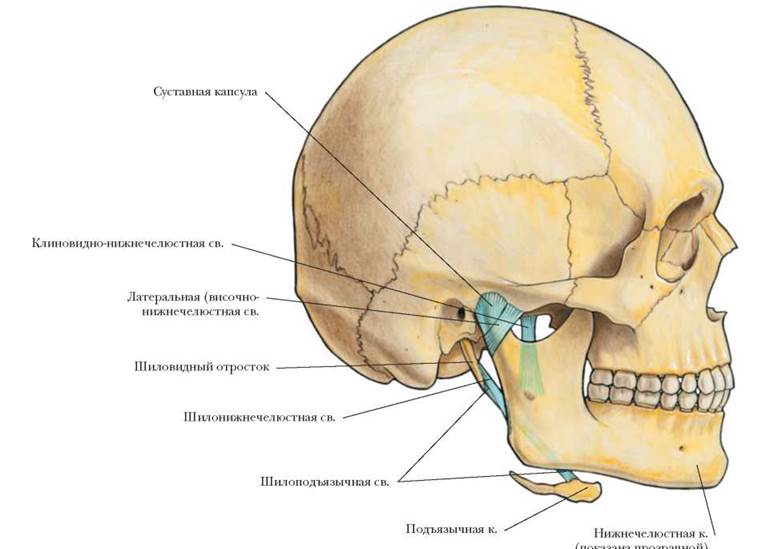

Анатомия детского черепа: Рентгеновские снимки и описание